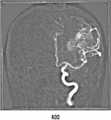

도 3b는 본 발명의 일실시예에 따라 획득된 조영제가 동맥을 통과할 때 제2영상의 예시도면이다.

FIG. 3B is an illustration of a second image when the contrast agent acquired in accordance with an embodiment of the present invention passes through an artery. FIG.

예를 들어, 상기 영상이 조영제를 주사하여 촬영한 혈류영상(즉, 혈관조영영상)인 경우, 시계열데이터는 특정시간 간격으로 획득된 제2영상(200) 프레임을 통해 측정된, 각 지점의 시간별 조영제에 의해 증강된 신호의 측정량 데이터일 수 있다. 혈관조영영상은 각 프레임마다 조영제에 의해 특정 영역이 증강된 2차원 영상을 포함하고 있다. 즉, 조영제를 주사하기 전에는, 도 3a에서와 같이, 조영 증강된 혈관영역이 존재하지 않다가, 동맥으로 조영제가 주사되면, 도 3b에서와 같이, 동맥영역이 밝아졌다가 시간이 흐름에 따라 조영제가 혈류와 함께 정맥쪽으로 이동하면서, 도 3c에서와 같이 정맥영역이 밝아지게 된다. 컴퓨터는 각 프레임 내에서 사용자가 선택한 특정한 지점(즉, 특정한 좌표)에 대응하는 밝기값을 추출한다. 상기 컴퓨터는 상기 추출된 밝기값을 각 프레임이 획득된 시간 순서에 따라 시계열데이터로 생성할 수 있다. 예를 들어, 혈관조영영상의 총 프레임 수가 n개인 경우, 1*N의 행렬을 생성하여 추출한 밝기 값을 순서대로 상기 행렬 내에 입력할 수 있다. 상기 컴퓨터는 상기 행렬 데이터를 바탕으로 그래프를 생성(plot)하는 등의 시계열 분석을 수행할 수 있다.For example, when the image is a blood flow image (i.e., an angiogram image) taken by scanning the contrast agent, the time series data may include time-series data measured through a

또한, 상기 시계열데이터(300) 제공단계(S400)는, 상기 사용자로부터 선택된 특정지점에 대한 상기 조영제 도착시점 이후 특정시점의 제1 또는 제2영상(200)을 표시하는 단계;를 포함할 수 있다. 도 3a 내지 도 3c에 도시된 바와 같이, 동맥으로 조영제를 주입한 후 통과되는 혈관의 위치에 따라 조영증강에 의해 강조되는 부분이 달라지게 된다. 의료진이 혈관 검사 시 혈관의 상태를 시각적으로 더 잘 파악하기 위해서는, 컴퓨터가 사용자로부터 선택된 특정지점을 많은 양의 조영제가 통과하여 선명하게 인식될 수 있는 제1 또는 제2영상(200)의 프레임을 화면에 표시해줄 필요가 있다. 따라서 컴퓨터는 시계열데이터(300)를 바탕으로 선택된 특정지점을 통과하는 조영제 양이 특정기준 이상인 프레임을 추출하여 표시하도록 할 수 있다.The step of providing the